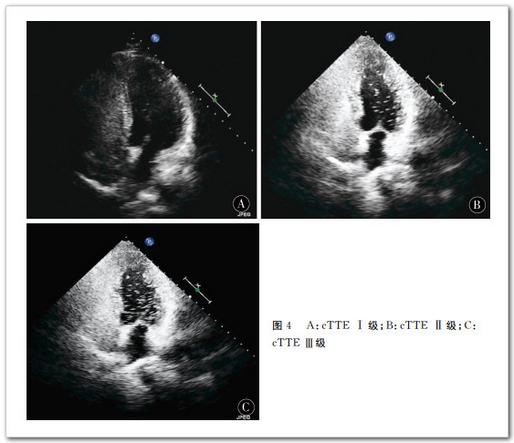

166 例 患 者 中 cTCD检 测 出 RLS80 例(48.19%),cTTE 检 测 出RLS68 例(40.96%),差异有统计学意义(P<0.005)。cTCD静息 状 态 下 检 测 出RLS27例(16.27%),Valsava动作后检测出RLS80例(48.19%)。Valsava动作后 RLS检出率明显高于静息状态(P<0.005)。cTTE静 息 状 态 下 检 测 出 RLS28例(16.87%),Valsava动作后检测出 RLS68例(41.76%)。Valsava动作后 RLS检 出 率 明 显 高 于 静 息 状 态(P<0.005)。cTCD 半定量分级结果:Ⅰ级少量分流26例(15.66%),Ⅱ级中量分流26例(15.66%),Ⅲ级大量分流28例(16.87%);cTTE半 定 量 分 级 结 果:Ⅰ级少量分流27例(16.27%),Ⅱ级中量分流19例(11.45%),Ⅲ级大量分流22例(13.25%)。两 种 检 查 方 法 的 分 级 结 果 差 异 有 统计学意义(Bowker检验值14.818,P=0.011),cTCD较cTTE检出 RLS级别高。

cTCD和cTTE均可发现患者是否存在右向左分流,判断右向左分流的程度,但cTCD和cTTE相比阳性率更高,Valsava动作后 RLS检 出 率 明 显 高 于 静 息 状 态,半定量分级结果有差异,cTCD较cTTE检出 RLS级别高。cTCD更适合作为RLS的初筛手段。